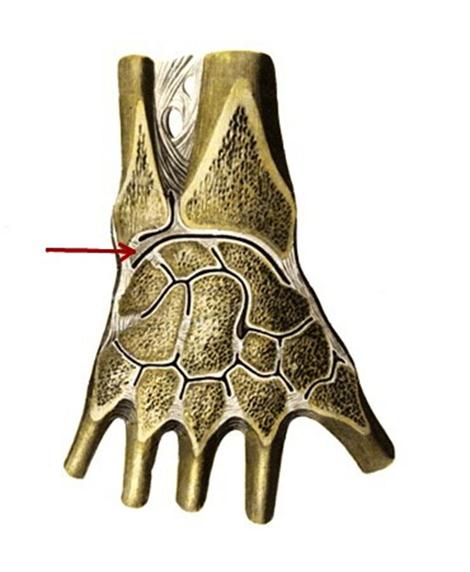

S: Стрелка указывает на art....

S: Стрелка указывает на art....

S: Стрелка указывает на art....

S: Стрелка указывает на art....

S: Стрелка указывает на art....

S: Стрелка указывает на …